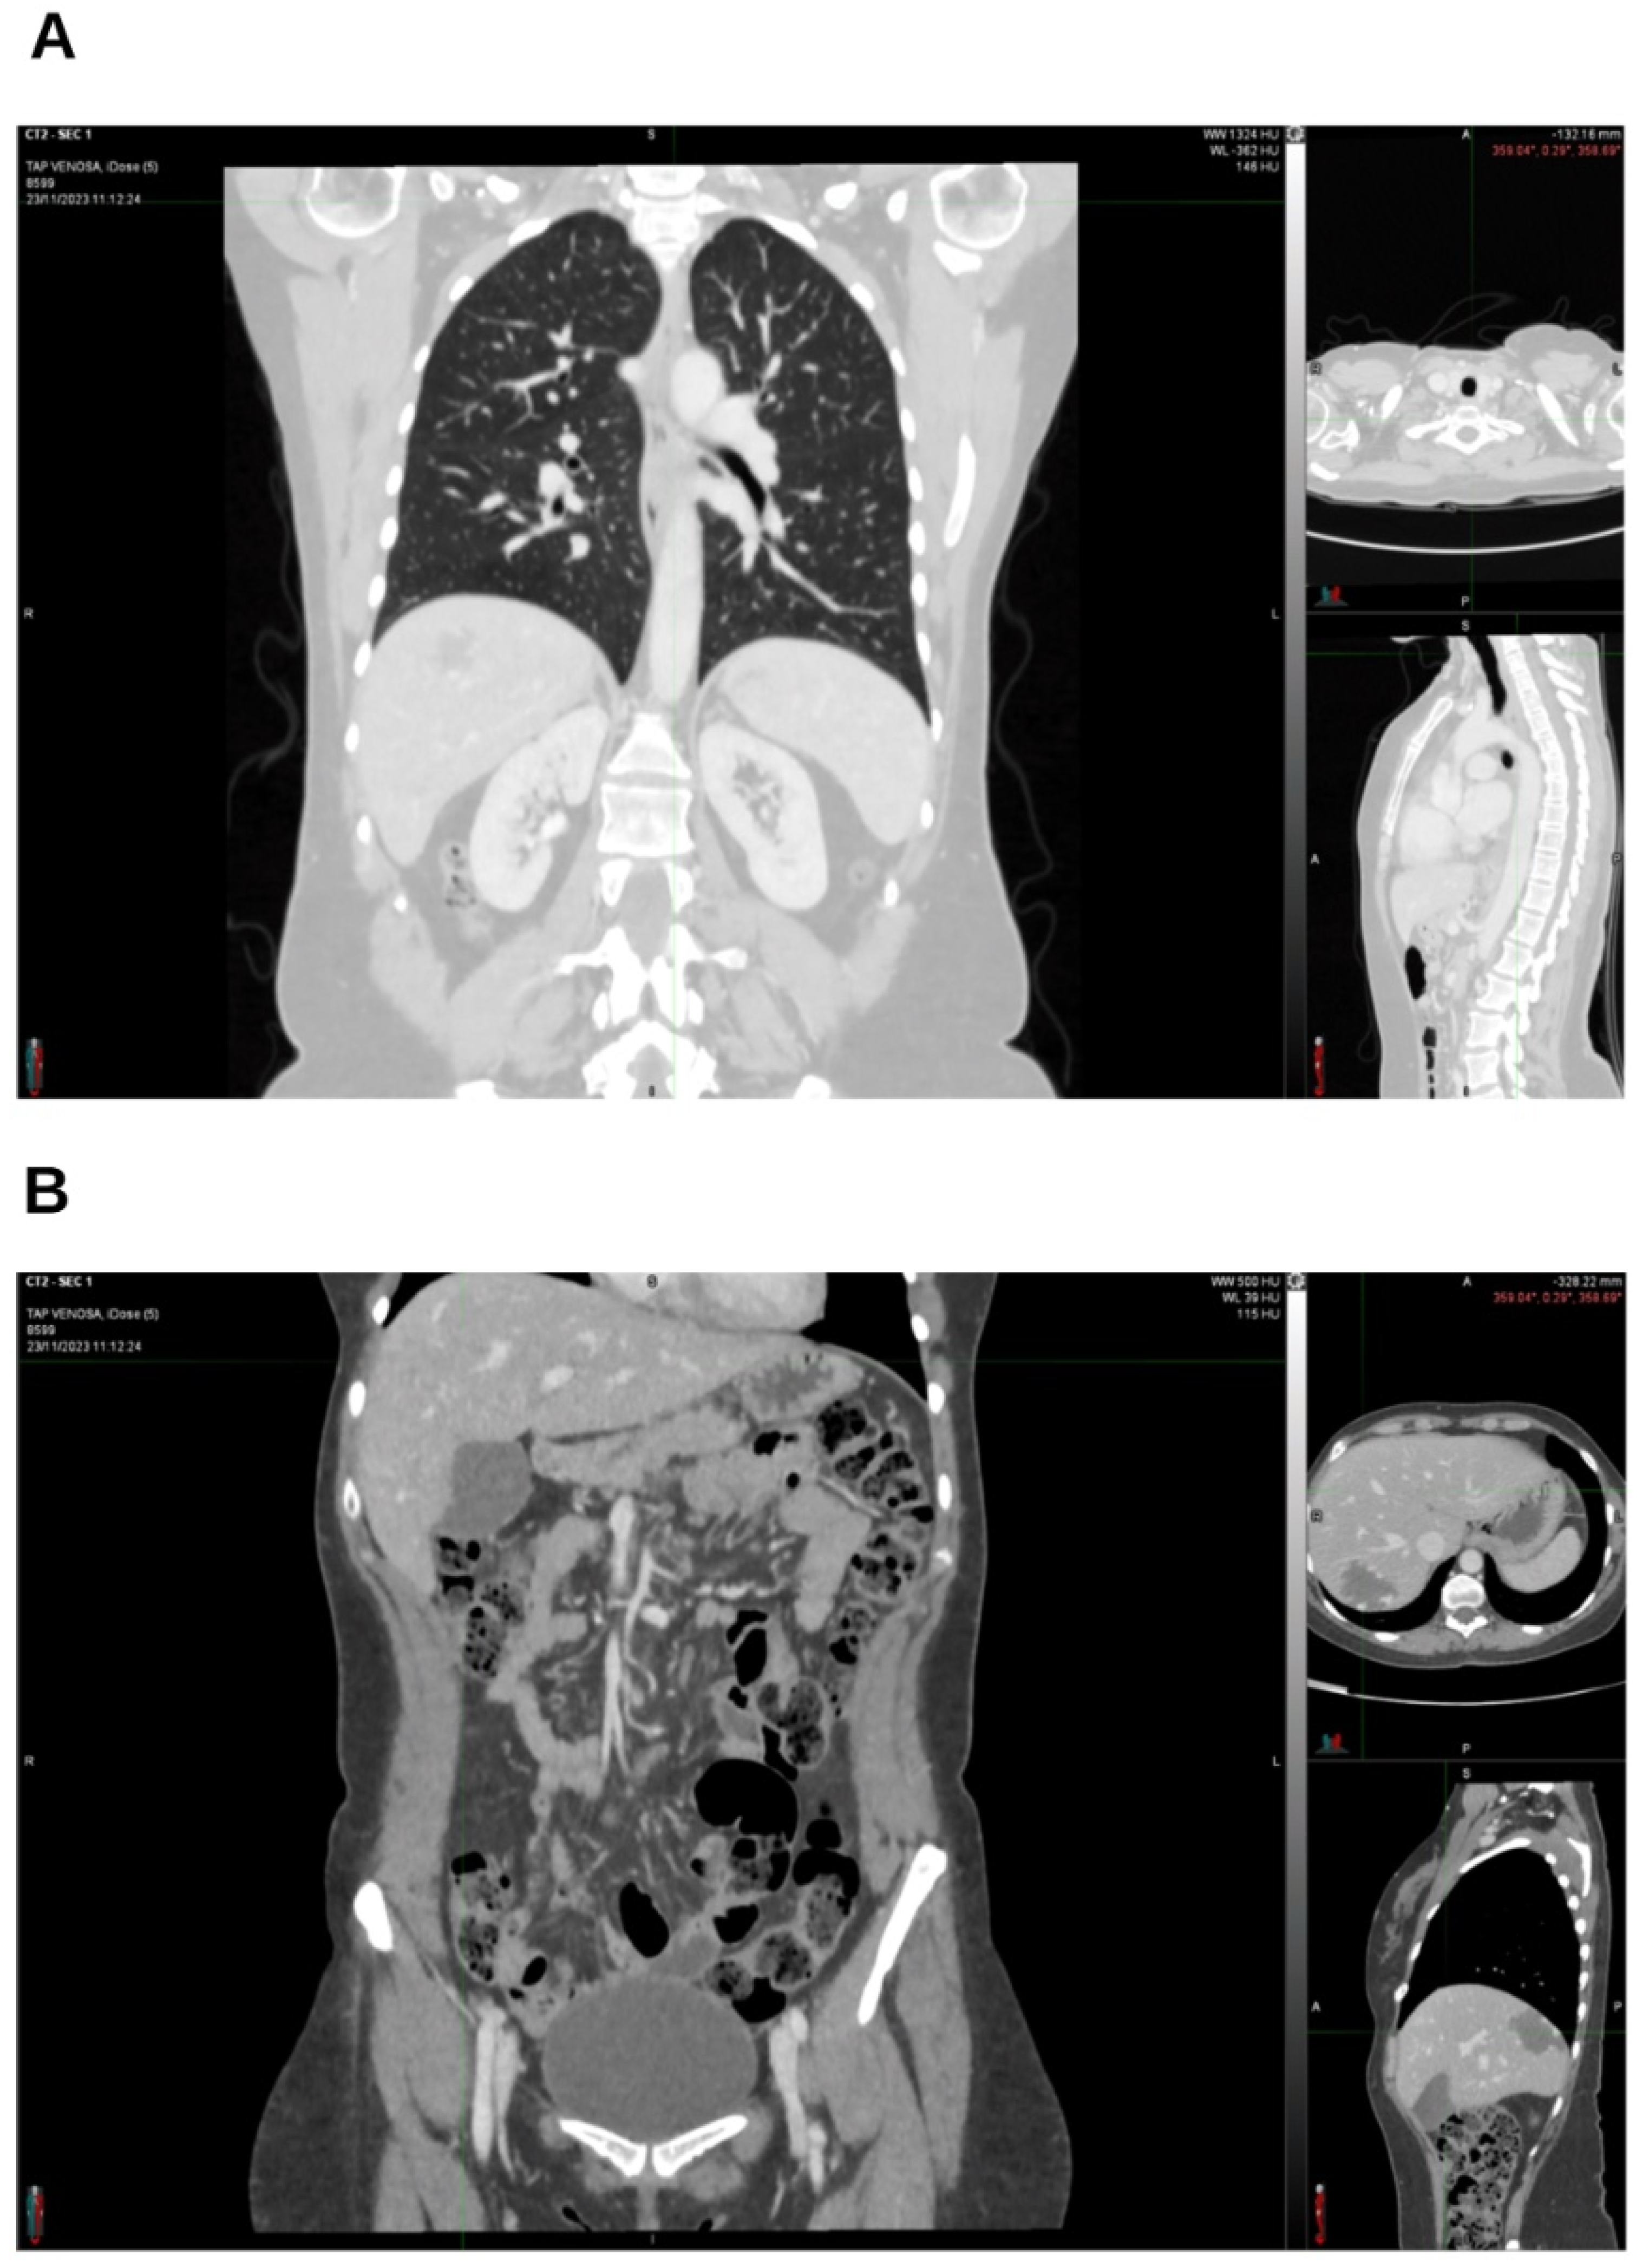

2. Case Presentation